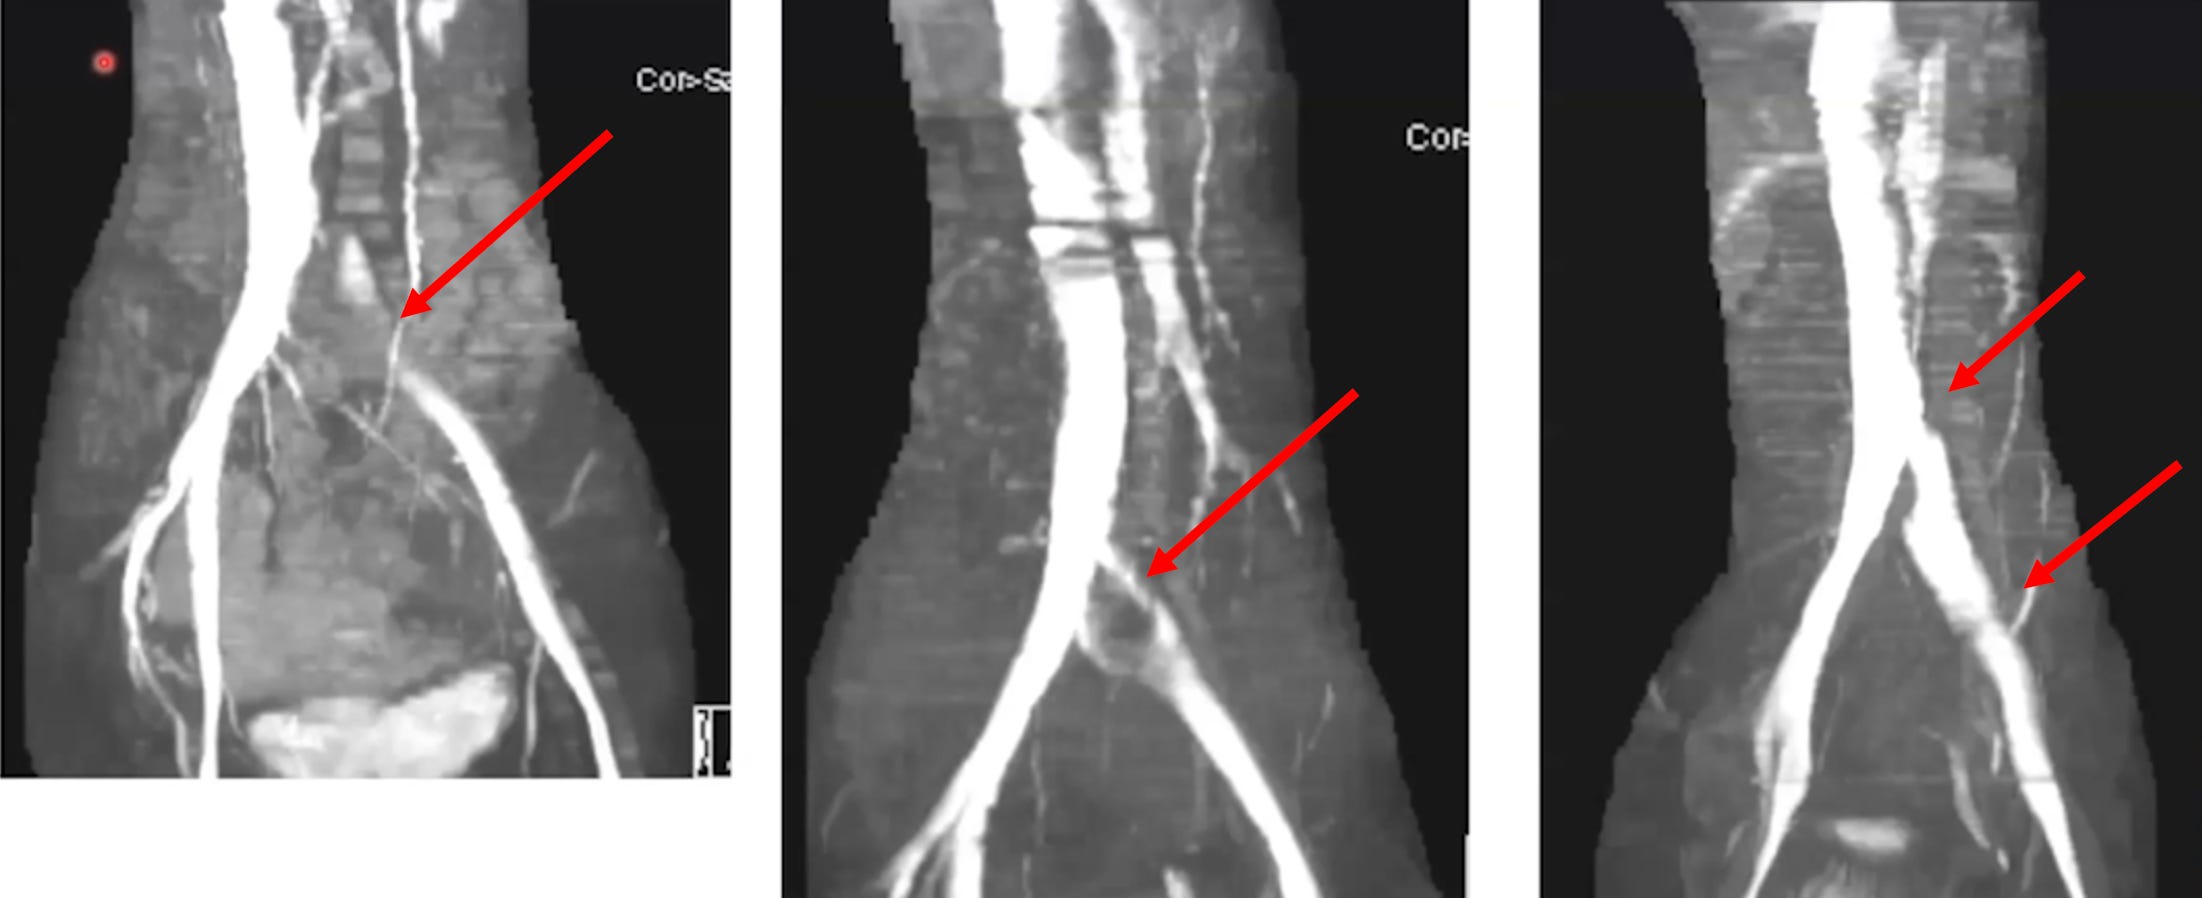

•Many of the debilitating complications of the COVID-19 vaccine appear to result from the iliac vein (which governs venous return from the legs and pelvis) becoming compressed and its blood supply becoming significantly obstructed (which in turn gives rise to numerous characteristic symptoms that can be recognized once one knows to look for them). More importantly, this compression can often onset quite suddenly and patients remember the exact moment that compression occurred.

•The blood flow obstruction created by an iliac vein compression appears to cause a variety of conditions which could be analogized to “putrid blood,” such as blood clots throughout the body and mast cell activation syndrome.

•A condition known as May-Thurner syndrome affects slightly over 20% of the population. In it, the (high pressure) right common iliac artery overlies and compresses the (low pressure) left common iliac vein against the lumbar spine

Normally, individuals with this syndrome do not notice it, but it some cases it can predispose them to unexpected blood clots (due to venous return being obstructed).

•Dr. Vaughan believes that the (well-documented) damage the spike protein causes to walls of the blood vessels weakens the iliac vein enough that pressure from the iliac artery can cause it to collapse. In turn, he has collected compelling radiography to prove it.

•If an iliac vein compression is treated with anticoagulation, this typically improves the symptoms of it, but once the anticoagulants are stopped, the symptoms return (as the source of the clotting has not been addressed). For this reason, iliac vein compressions are often treated with stenting, which Dr. Vaughan reports frequently significantly benefits patients.